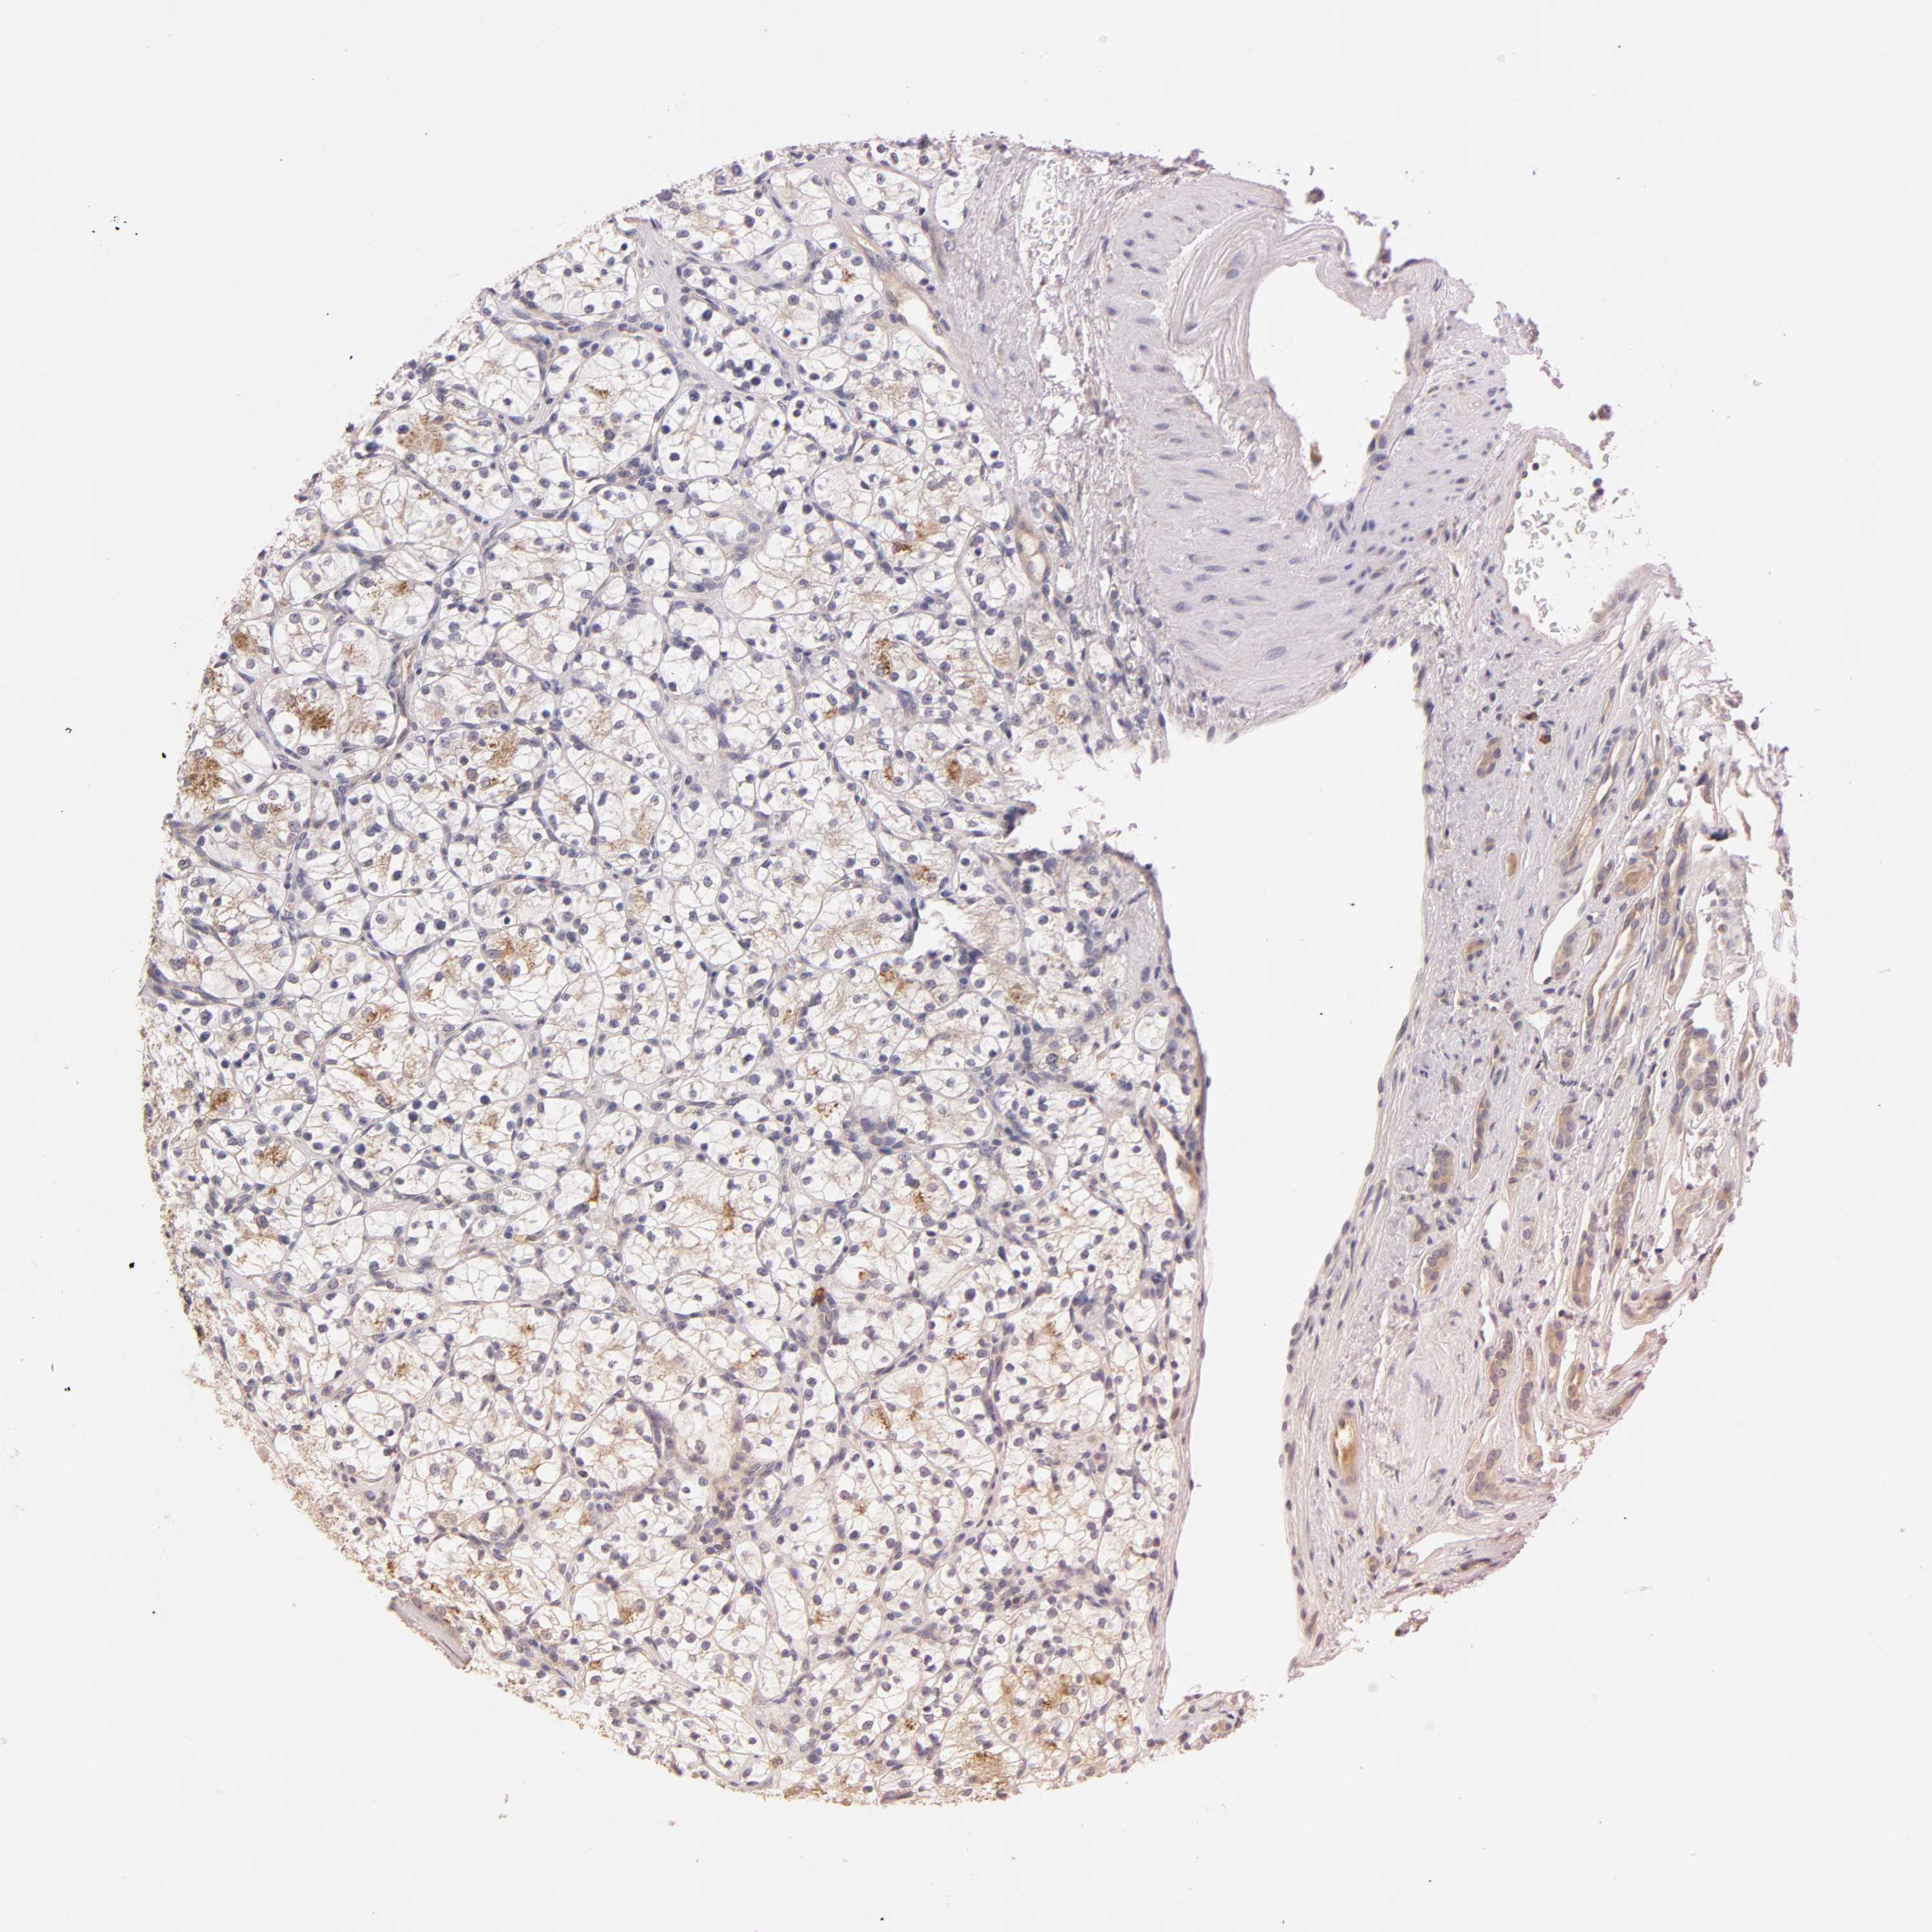

KIDNEY RENAL CLEAR CELL CARCINOMA (VALIDATION) - Interactive survival scatter ploti

RPS29 is not prognostic in Kidney Renal Clear Cell Carcinoma (validation)

: 2132.78

Average pTPM 2288.4

Number of samples 100